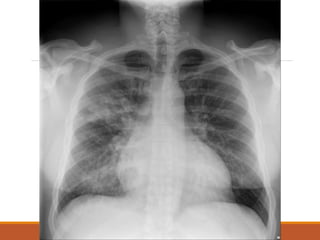

• Imaging : CXR

• #31 bronchopneumonia

• #32 Lobar pneumonia

• #33 ards